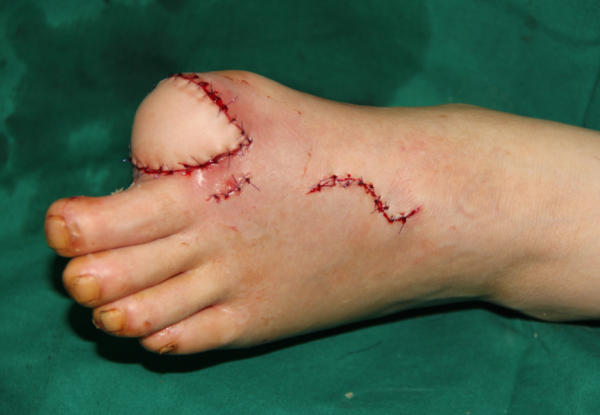

玉米机伤右足复合组织缺损,腓骨皮瓣修复,术后12天,伤口愈合良好,今日出院清创后

术后即刻

术后12天,没有感染